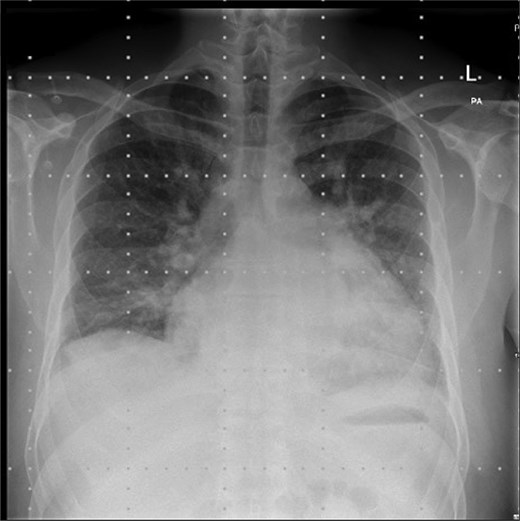

Chest radiograph demonstrated pulmonary oedema (Fig. 1) and transoesophageal echocardiography (TOE) demonstrated a flail P2 segment with an anteriorly directed jet of severe MR, vena contracta 8 mm, effective regurgitant orifice area 0.55 cm2 (Fig. 2). Left ventricle was severely dilated (LVEDD 72 mm) with ejection fraction 35%. Both atria and the left ventricle were dilated. No vegetations were seen. He was cardioverted to sinus rhythm with 200 J biphasic shock.